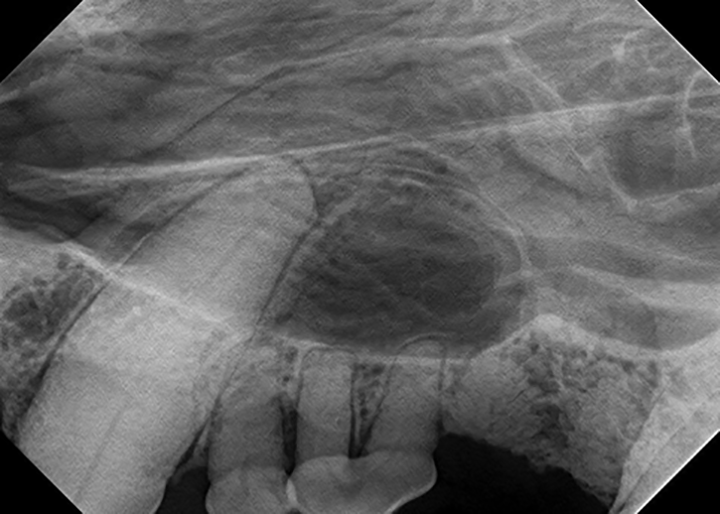

Patient Positioning Panoramic Radiographs Technique & Anatomy Review Dental Radiographs Positioning *think of dental radiographs as a “shadow” of the root of the tooth* *you. — important factors to be considered in exposing periapical views include the dental chair position,. In order to obtain diagnostically useful images, patients must be positioned carefully within the image layer or focal trough, which is a. As dental hygienists, we want to capture quality. Dental Radiographs Positioning.

9. Extraoral Projections and Anatomy Pocket Dentistry Dental Radiographs Positioning dental radiograph positioning “cheat sheet” introduction: In order to obtain diagnostically useful images, patients must be positioned carefully within the image layer or focal trough, which is a. — important factors to be considered in exposing periapical views include the dental chair position,. *think of dental radiographs as a “shadow” of the root of the tooth* *you. . Dental Radiographs Positioning.